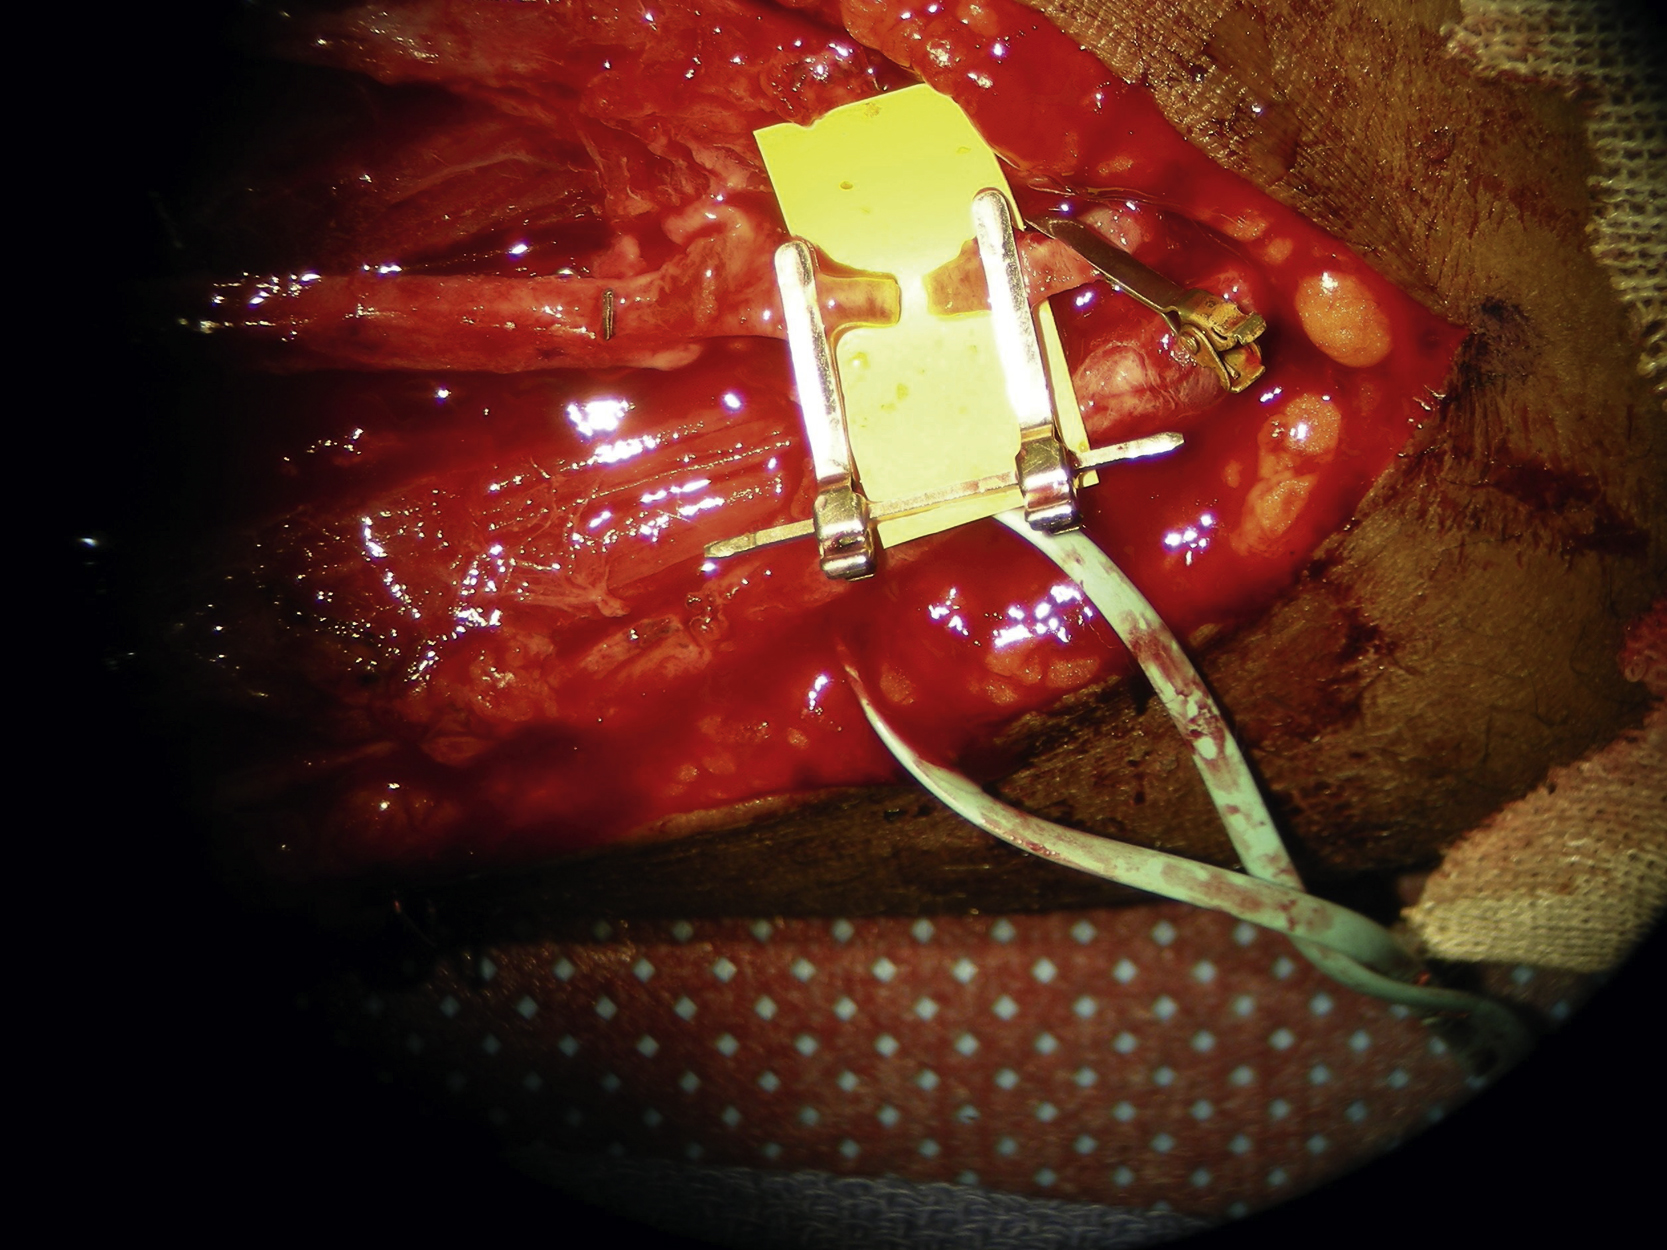

The pedicle was prepared under loop magnification. One artery and two veins were identified. The artery was flushed with heparinized saline solution. One good vein was selected for microvascular anastomosis. Both microvascular anastomoses were performed under a microscope. The arterial microanastomosis to the radial artery stump was performed in an end-to-end fashion with interrupted 8-0 nylon sutures ( Fig. 18.5 ). The venous microanastomosis to the superficial antecubital vein was also performed in an end-to-end fashion with a 2-mm coupler ( Fig. 18.6 ). Once all the clamps had been released, the flap appeared to be well perfused. The flap was temporarily inset into the forearm wound.